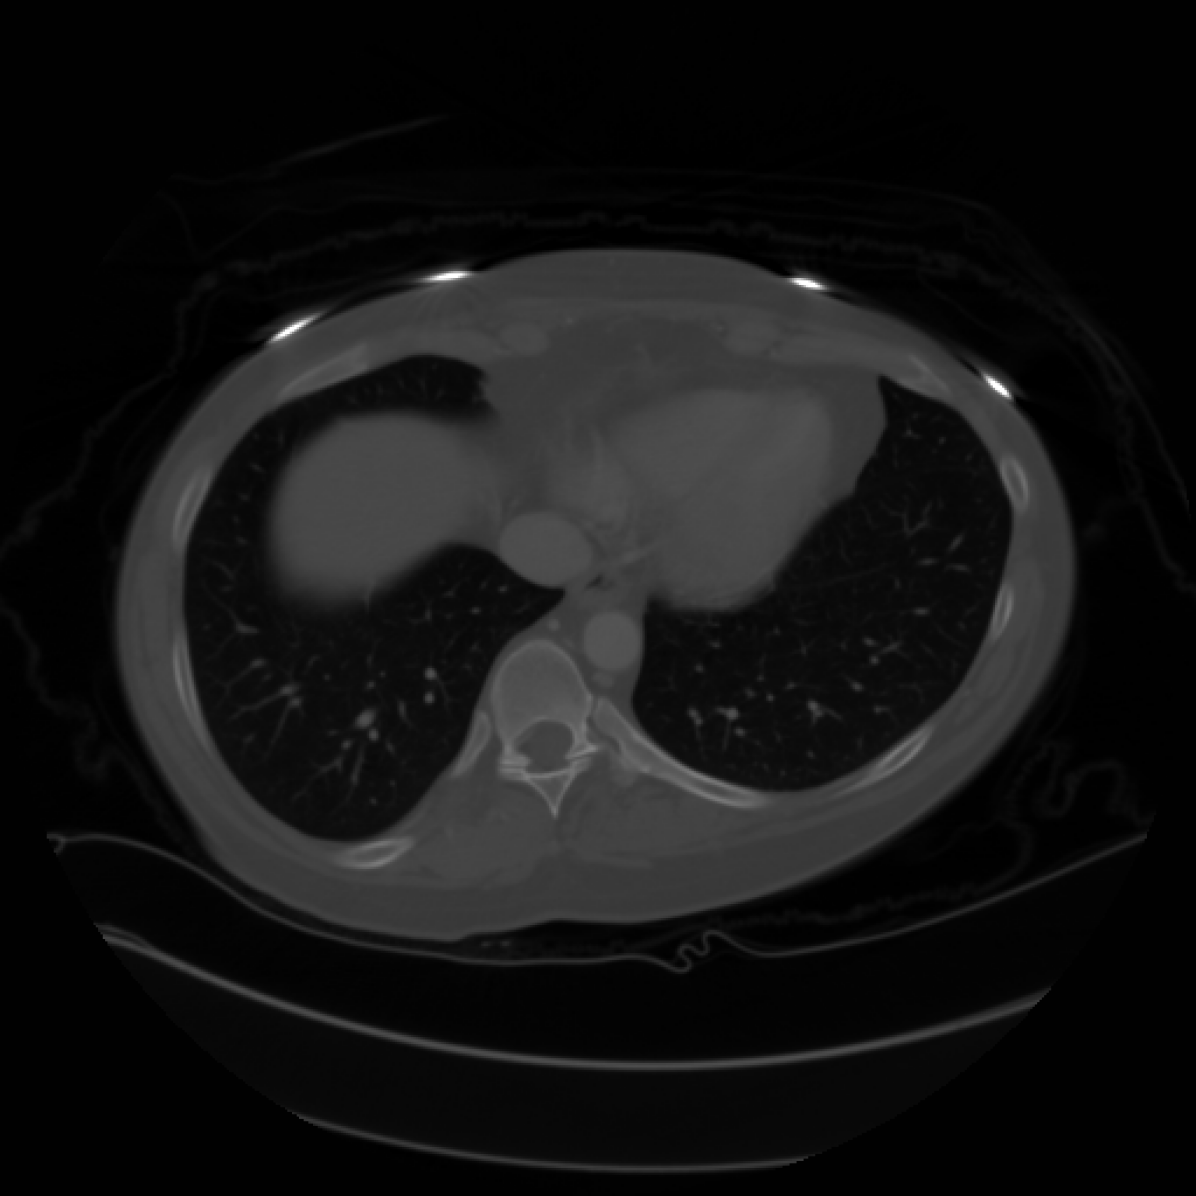

In this section we will show qualitative results of DINOv2 features using principal component analysis (PCA) performed on DINOv2 patch features on X-ray, CT, and MRI scans, following the method delineated in [8]. We will also provide organ segmentation results of linear compared U-Net decoders.

PCA visualization. Figure 2 shows the first three PCA components. The PCA is computed between patches of images that are in the same column, and the first 3 components are shown for X-ray, CT, and MRI scans. Thresholding is used on the first PCA component to remove the background. Just like in natural images [8], the colors of the three PCA components correspond well with the same parts of images in the same category. This is an easier task however, compared to natural images, because there is less variability between examinations on medical images compared to natural images.